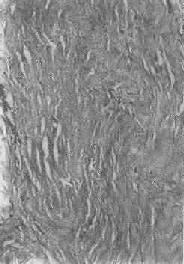

纤维瘢痕组织的玻璃样变

图1-19 纤维瘢痕组织的玻璃样变

胶原纤维变粗,互相融合呈均质梁状

1.结缔组织玻璃样变:常见于纤维瘢痕组织、纤维化的肾小球,以及动脉粥样硬化的纤维性瘢块等。此时纤维细胞明显变少,胶原纤维增粗并互相融合成为梁状、带状或片状的半透明均质,失去纤维性结构(图1-19)。质地坚韧,缺乏弹性。玻璃样变的发生机制尚不甚清楚,有人认为在纤维瘢痕老化过程中,原胶原蛋白分子的交联增多,胶原原纤维也互相融合,其间并有较多的糖蛋白积聚,形成所谓玻璃样物质;也有人认为可能由于缺氧、炎症等原因,造成局部pH升高或温度升高,致使原胶原蛋白分子变性成明胶并互相融合所致。